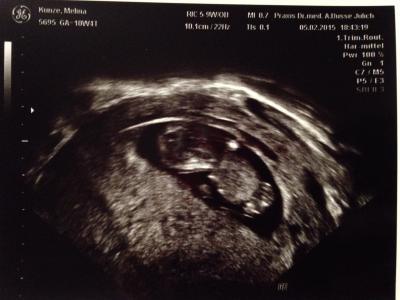

Wir hatten ja heute endlich wieder Baby-TV :-) Der kleine Alien ist fleißig gewachsen, jetzt ca. 4cm groß und alles ist da wo es hingehört, ich hab sogar die winzigen Zehen gesehen :-))) Ist von der Größe auch schon 2 Tage weiter, aber sie hat den ET jetzt nicht geändert und will sich erst beim nächsten Termin festlegen, da ist dann auch das ETS. Bin total froh und erleichtert und hab erst nach dem Termin gemerkt wie mir das die letzten Tage (unterbewusst) zu schaffen gemacht hat, ich fühl mich wie beflügelt:-) Freue mich für alle die heute auch einen positiven Termin hatten und drücke allen die Daumen, die morgen (also eigentlich schon heute) dran sind!